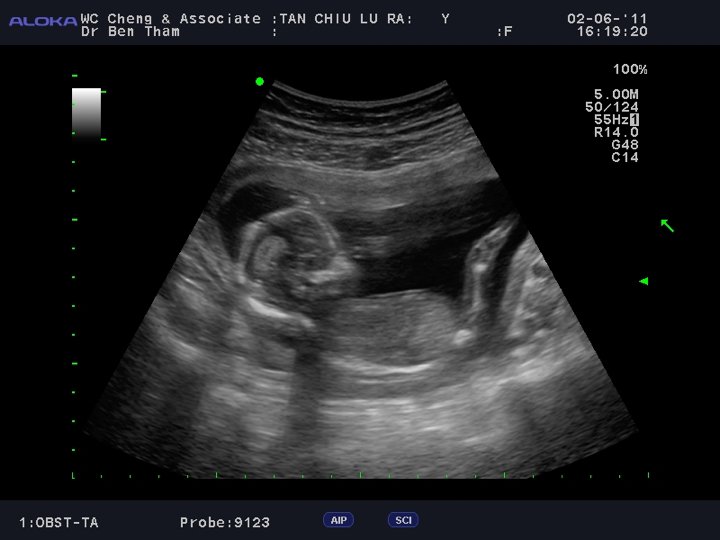

Jah at 4 months… on mummy’s birthday (2 June 2011)

While I was fortunate enough not to be plagued with horrible morning sickness, I basically had ‘whole day sickness’ till the 20th week or so which pretty much stopped me from eating most things or anything. I didn’t puke but I also didn’t feel like eating anything at all. I didn’t put on any weight in my initial months of pregnancy but thankfully Jah continued to gain weight and he was a whooping 3.6kg (based on the scans) by the time we were at 36 weeks.

So yes we were pretty eager to have him out, like most first time parents normally are (until they realize its really easier if they stayed in :p) Also because of an old back injury (fractured tailbone), I was very worried that my tailbone would snap again during labour if Jah turned out to be too big.